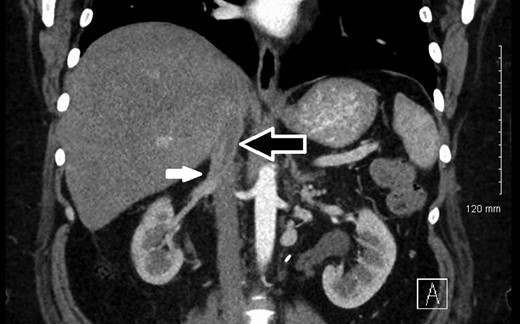

The patient was followed with serial imaging for the next 6 years when a recurrent mass was noted in the retrohepatic IVC. The tumor originated just above the renal veins and extended into the hepatic veins (Fig. 1). At this point she was referred to the University of Colorado for further evaluation. Her work-up included CT angiogram and an magnetic resonance imaging (MRI) of her liver. The CT showed a 4 cm by 3 cm intracaval mass at the level of the IVC-hepatic vein confluence. An additional 9-mm nodular mass was noted within the cava raising the possibility of dis-contiguous disease (Fig. 1). Following appropriate preoperative counseling, the patient was taken to the operating room for surgical resection. Extensive lysis of adhesions was performed from a large midline incision. Following complete mobilization of the liver, and control of the suprahepatic and infrahepatic cava, she underwent segmental resection of the IVC between the renal and hepatic veins with reconstruction using a 24-mm Dacron tube graft. All grossly visible tumor was removed (Fig. 2).

Preoperative CT identifying a smooth, well-circumscribed mass within the IVC arising superior to the right renal vein long (white arrow) and terminating just prior to right hepatic take-off (black arrow).